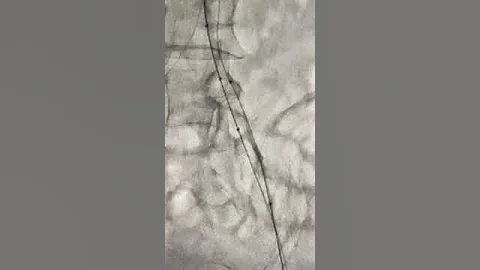

8.3.6: Manual Of Cto Pci - Reverse Cart Troubleshooting

Seven solutions for difficult to complete reverse CART (can be used in various combinations): 1. Change the target (use a guide ...